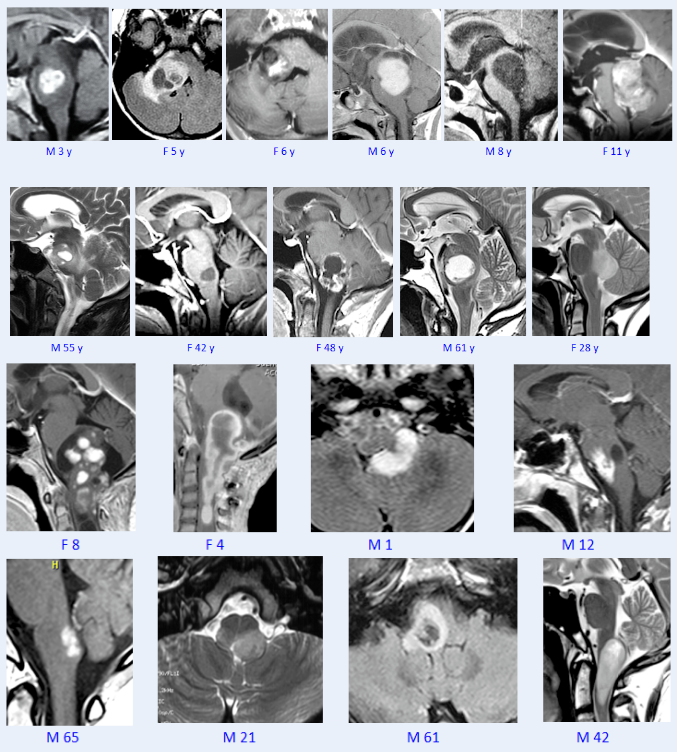

此次峰會(huì)上,巴教授精選其206例腦干膠質(zhì)瘤案例進(jìn)行了詳細(xì)的分享,其中大多數(shù)是低級(jí)別的毛細(xì)胞型星形細(xì)胞瘤。究竟哪些腦干膠質(zhì)瘤可以手術(shù),巴教授手術(shù)后預(yù)后如何?

手術(shù)效果最好的腫瘤當(dāng)然是毛細(xì)胞型星形細(xì)胞瘤,因?yàn)樵谶@些腫瘤中,我們可以找到清晰的邊界,即使腫瘤體積非常大,就像我們?cè)谶@里看到的那樣,我們也能找到清晰的邊界。與其他腫瘤相比,它是一種良性腫瘤。它不會(huì)彌漫性地長到腦干內(nèi),所以會(huì)有一個(gè)邊界,它們是很好切除的。

巴教授毛星手術(shù)案例系列分享